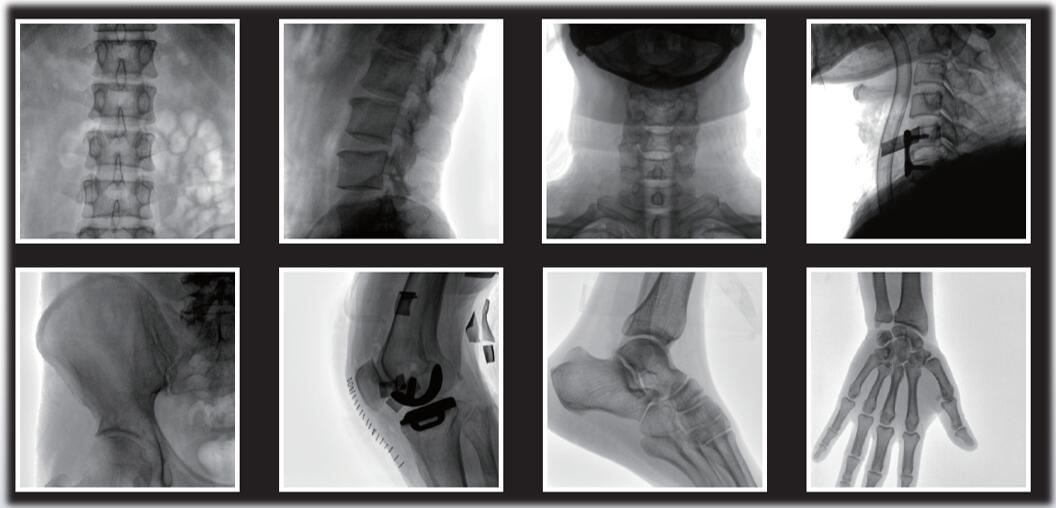

小C臂又稱骨科C臂,是指機(jī)架為C型的X線影像設(shè)備,用于手術(shù)中的實(shí)時(shí)動(dòng)態(tài)成像。說起平板小C臂,大家印象大多是圖像清晰、電動(dòng)控制、大開口廣闊空間、顏值高等。確實(shí),平板小C臂在骨科手術(shù)中的定位、診斷、微創(chuàng)手術(shù)的開展與治療中發(fā)揮獨(dú)特的作用。作為一名醫(yī)生,您需要清晰的圖像質(zhì)量來幫助您應(yīng)對(duì)更具挑戰(zhàn)性的手術(shù)。

大尺寸動(dòng)態(tài)平板探測(cè)器,圖像清晰細(xì)膩,滿足臨床多種檢查。

采用了多分辨率圖像增強(qiáng)處理技術(shù),不同部位不同圖像處理。

平板小C臂與影增小C臂相比,有明顯優(yōu)勢(shì):圖像更穩(wěn)定清晰,視野更好,軟件算法也更加高深。相比于影增小C臂, ?平板小C臂的成像原理中避免了信號(hào)轉(zhuǎn)換中的損失, 提高了X射線的利用率, 成像速度大幅度提高, 獲得所需圖像信息的時(shí)間更短, ?輻射劑量和輻射時(shí)間也隨之降低。PLX118系列平板小C臂為您提供優(yōu)良的圖像、靈活的操作體驗(yàn)和更低的劑量表現(xiàn)。如果您想采購(gòu),或了解產(chǎn)品具體參數(shù),可關(guān)注“普愛醫(yī)療”。